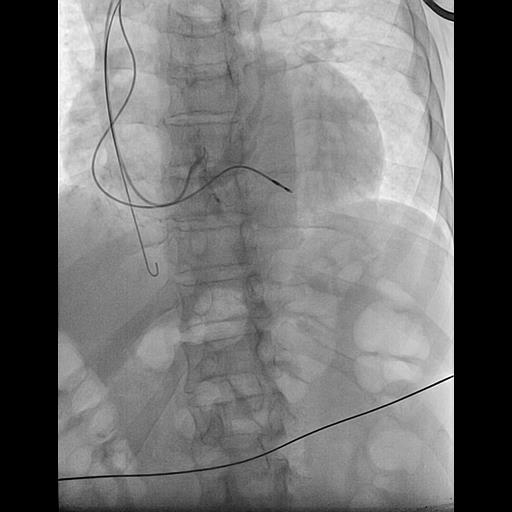

@ShaojieChen1 @hrs_journal @dredcronin @TJaredBunch @d_changy @DanielPMorin @drrakeshg1 @Maeskander @senthil_dorai @DrRoderickTung @pjsm83 @mencardio @ZS279 @clementy_ep @MBergonti @Anand_Ganesan1 @RawahiAl @javadm20 @rdschaller @SchakrabartiEP @EJSMD @LaredoMikael @ugurcanpolatmd @ChiaraValeriano @MDerndorfer @ecgrhythms @adribaran @Basalus @jvillacastin @DrGregMichaud nsHBP, sHBP, LVSP, sLBBP, nsLBBP, LBBAP, LVSP, RVSP, nsRBBP, sRBBP, what should we look forward to next?